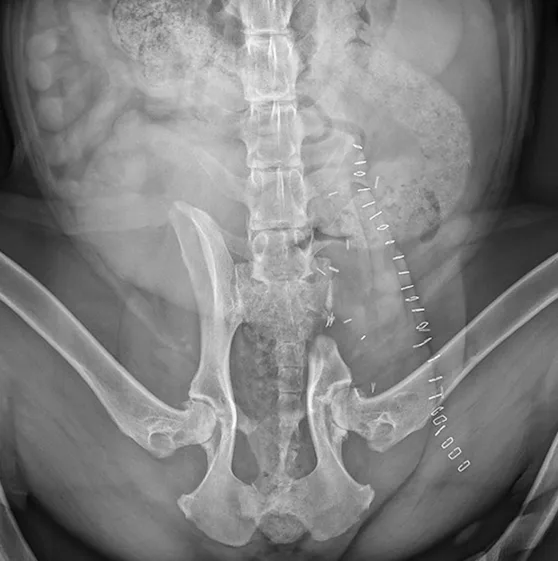

FIGURE 4

Ventrodorsal postoperative radiograph showing the removal of the affected portion of the left ilium

Treatment

Left iliectomy and stereotactic radiosurgery were suggested to provide curative-intent local control of the tumor. Palliative radiation was also discussed. The owners elected iliectomy and preservation of the left pelvic limb; the left ilium was resected via sacroiliac disarticulation (Figure 3), and the left acetabulum and left pelvic limb were preserved. Postoperative radiographs showed adequate tumor removal (Figure 4).